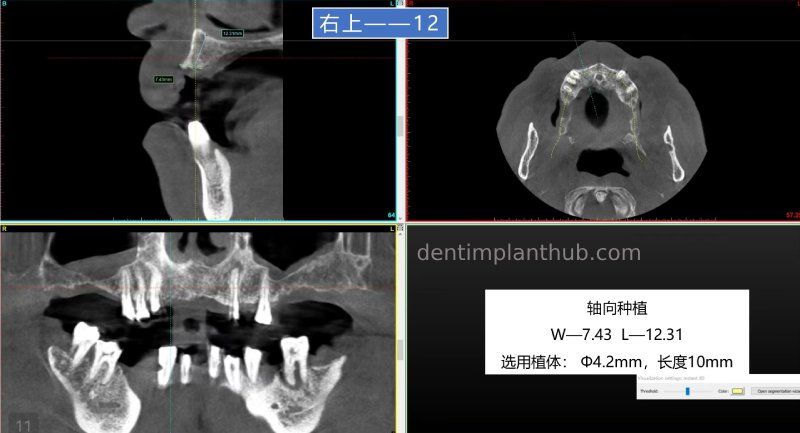

12, 22 normal implantation;

12, implant model 3810;